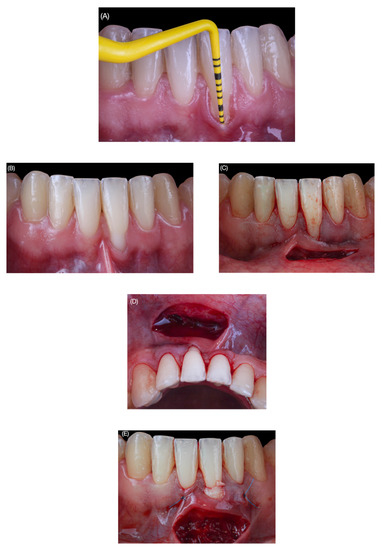

Figure 1.

(A) Man with recession at the mandibular left central incisor, before the prophylaxis appointment. (B) Preoperative view, 2 weeks after prophylaxis appointment. (C) Apical horizontal incision at a distance (2GR + 2 mm) from the gingival margin with recession. (D) Occlusal view. Horizontal incision made at partial thickness extending from mesial of the right central incisor to distal of the left lateral incisor. (E) Connective tissue graft sutured at the level of the CEJ using two horizontal mattress sutures. (F) Note the coronally repositioned flap and the palatal protection plate. (G) Occlusal view. Crossed horizontal mattress suture anchored in the periosteum. No suture was placed along the horizontal incision, to allow healing by second intention. (H) Lateral view. The flap, made predominantly of alveolar mucosa, was advanced coronally to completely cover the connective tissue graft. (I) After 1 month of follow-up.

All surgeries were performed by the same experienced periodontist (NQ), using the bridge flap technique with CTG. Prior to surgery, patients were required to rinse their mouths for 1 min with 0.12% chlorhexidine mouthwash +0.05% CPC (Perio-Aid, Dentaid, Barcelona, Spain). After local anesthesia, the surgical technique began with preparation of the recipient area: a partial-thickness sulcular incision was made at the level of each recession/s using a micro-scalpel (Spoon Blade, MJK instruments, Marseille, France), dissecting apically beyond the mucogingival junction and laterally under each papilla without cutting it, extending 3 to 5 mm from each recession/s. Subsequently, a horizontal incision was made using a 15C scalpel blade (Swann-Morton, Sheffield, UK) in the alveolar mucosa of the bottom of the vestibule, leaving a bridge of tissue that was to serve later for a double blood supply to the CTG. The horizontal incision extended one tooth on either side of the tooth/teeth with recession/s and was made at a minimum distance of 8 mm from the gingival margin of the tooth with recession (Figure 1B–D).

To calculate the distance at which the horizontal incision should be made, the formula proposed by Romanos et al. [28] (2 × GR + 2 mm) was used as a reference. The tissue coronal to the horizontal incision was subsequently repositioned apico-coronally, maintaining the marginal integrity of the tissue. The root surface was then mechanically decontaminated using Gracey curettes, treating only the exposed root surfaces with clinical attachment loss.